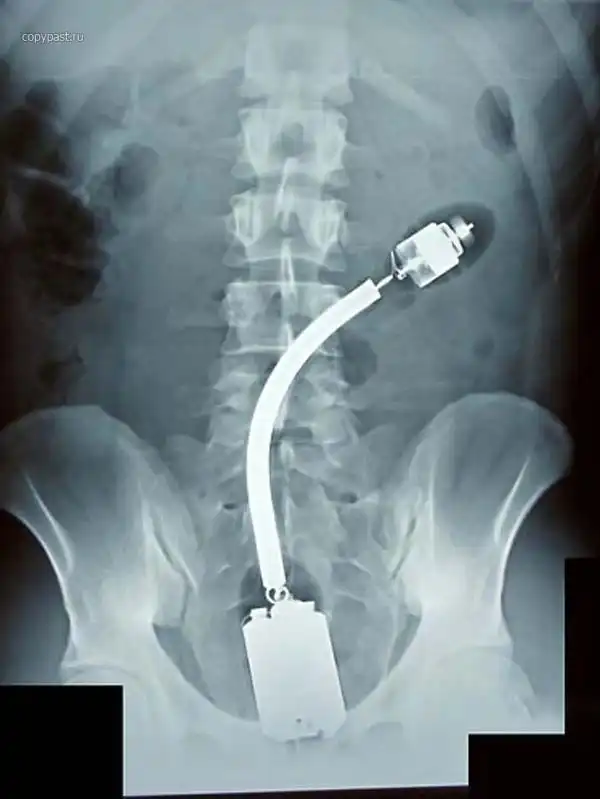

Огромный вибратор в заднице. Залез полностью. Без хирургического вмешательства

достать не смогли. Больные люди...